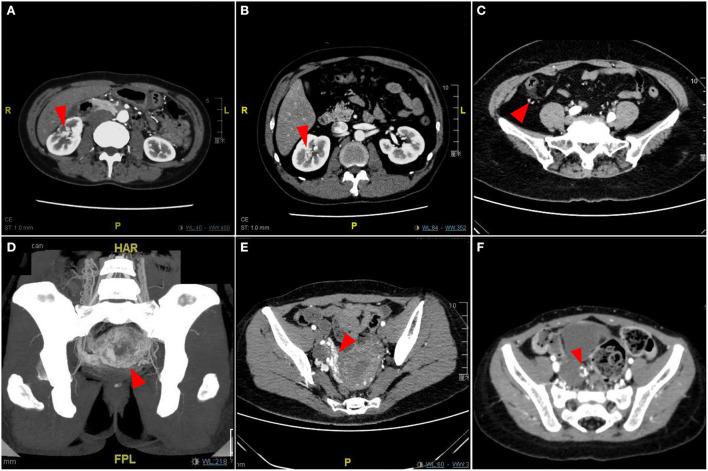

RESULTS

纳入2016年3月27日至2021年3月31日期间诊断为单纯性pAVM的中国患者。患有中枢神经系统单纯性动静脉畸形(cnsAVM)、AVM合并类型以及CLOVES综合征等综合征的患者均被排除在本研究之外。共筛选出1070例单纯性pAVM患者。所有单纯性pAVM患者均通过临床表现和影像学检查确诊。人口统计学数据来自中国国家统计局。单纯性pAVM的5年患病率约为(2.15 - 6.60)/100万人口。男女比例约为1.22:1。年龄在21至30岁组的pAVM住院患者构成比最高( = 0.01)。分类包括四组:I型(主要发生于软组织);II型(主要发生于骨骼);III型(主要发生于脏器)和IV型(单纯性pAVM合并中枢神经系统病变)。I型有两个亚型:A亚型(累及一个主要解剖区域)和B亚型(累及两个或更多主要解剖区域);II型有两个亚型:A亚型(皮质完整)和B亚型(病变已突破皮质)。一般来说,657例患者被分类为IA型(61.4%),232例为IB型(21.7%),82例为IIA型(7.7%),79例为IIB型(7.4%);患有III型和IV型pAVM的患者数量分别为9例(0.8%)和11例(1.0%)。还系统总结了各类型的临床表现和诊断标准。